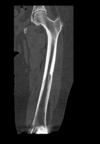

Osteoma Osteóide - A TC mostra o nidus radioluscente, cercado por reação esclerótica e , as vezes, pode mostrar um ponto esclerótico dentro do nidus.

Predomina 10 - 30 anos.

Nicho radiotransparente < 1cm circundado por reação esclerótica. Localização cortical / justacortical em ossos longos: femur proximal e tibia.

Clinica tipica: dor mais intensa a noite aliviada por AAS.

Quando nidus > 2cm = osteoblastoma. TC é a modalidade de escolha (RM pode não ver o nidus).